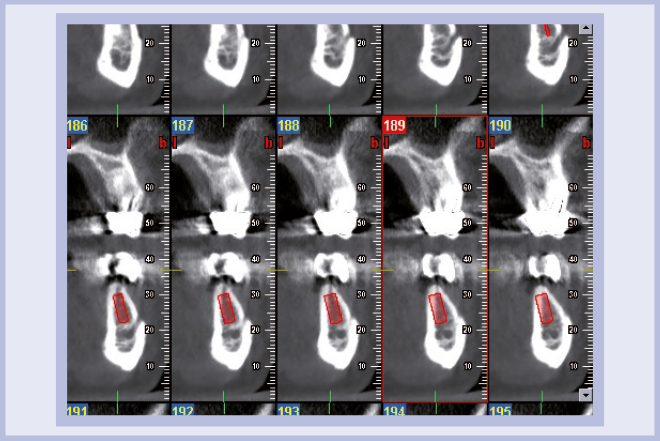

Viene quindi richiesto al tecnico di modificare in laboratorio la mascherina radiologica mediante il posizionamento delle boccole di guida adatte agli impianti da posizionare (Exacone® 6.5 e Exacone® 3,3×8) in asse con gli analoghi del modello Master 3D ed eliminando il repere radiologico standardizzato, trasformandola così nella dima chirurgica (Figg. 14, 15). Si procede quindi alla prova della mascherina sulla paziente per verificarne la stabilità e la corrispondenza esatta con il modello Master 3D (Fig. 16). La seduta chirurgica con tecnica flapless, guida chirurgica e Frese Zero1 dedicate non presenta alcuna difficoltà ; al termine dell’inserimento si posizionano sugli impianti tappi di guarigione bassi per permettere loro di guarire con tecnica sommersa (Figg. 17-27). Si effettua nella stessa seduta una CBCT che dimostra che la posizione clinica degli impianti risulta sovrapponibile a quella progettata dagli Autori (Figg. 28-30).

- Figg. 28, 29 – Verifica radiografica 3D subito dopo l’inserimento degli impianti

- Fig. 29

- Fig. 30 – Confronto tra posizione progettata e posizione clinica degli impianti: si noti la stretta corrispondenza tra il progetto e la CBCT post-operatoria